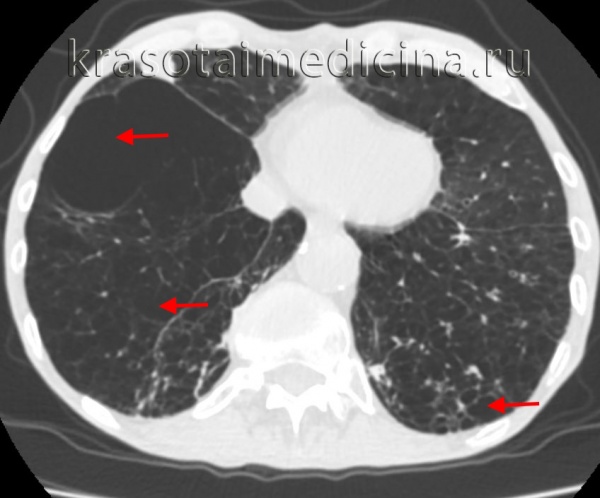

- Компьютерная томография. КТ ОГК производится для уточнения характера повреждений, выявления ателектазов, пневмо- и гемоторакса, других патологий, выполняется нативно или с контрастом. Пациентам также могут быть показаны КТ легких или КТ средостения. Для детализации изменений, обнаруженных на рентгенограммах костей лица, могут быть назначены КТ орбиты и другие исследования.

Кроме этого, буллы могут быть солитарными и множественными, одно– и двусторонними, напряженными и ненапряженными. По распространенности в легком дифференцируют локализованную (в пределах 1-2-х сегментов) и генерализованную (с поражением более 2-х сегментов) буллезную эмфизему. В зависимости от размера буллы могут быть мелкими (диаметром до 1 см), средними (1-5 см), крупными (5-10 см) и гигантскими (10-15 см в диаметре). Буллы могут располагаться как в неизмененном легком, так и в легких, пораженных диффузной эмфиземой.

Диагностика буллезной эмфиземы легких основывается на клинических, функциональных и рентгенологических данных. Курация больного осуществляется пульмонологом, а при развитии осложнений – торакальным хирургом. Рентгенография легких не всегда эффективна в выявлении буллезной эмфиземы легких. В то же время, возможности лучевой диагностики существенно расширяет внедрение в практику КТ высокого разрешения. На томограммах буллы определяются как тонкостенные полости с четкими и ровными контурами. При сомнительном диагнозе удостовериться в наличии булл позволяет диагностическая торакоскопия.